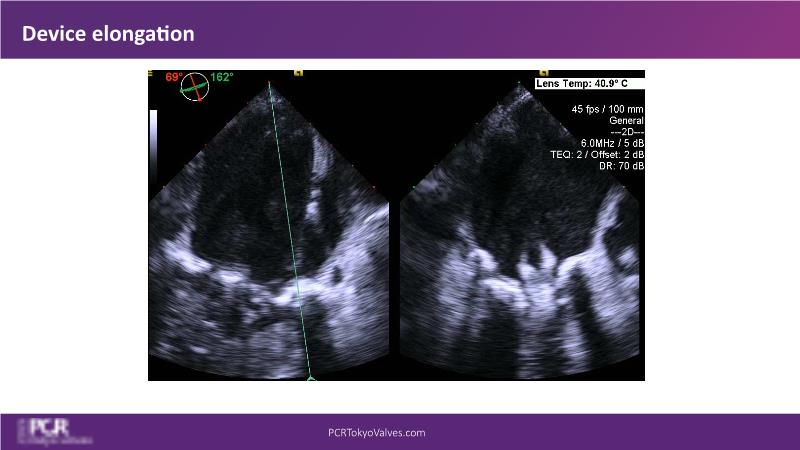

Watch this session to get an overview of a new TEER device, follow the step-by-step procedure related to initial experiences with this device for a Japanese patient with degenerative mitral regurgitation, learn about the latest data from RCT and registries, and follow discussions of challenging TEER cases!

- To learn procedural step-by-step of novel device